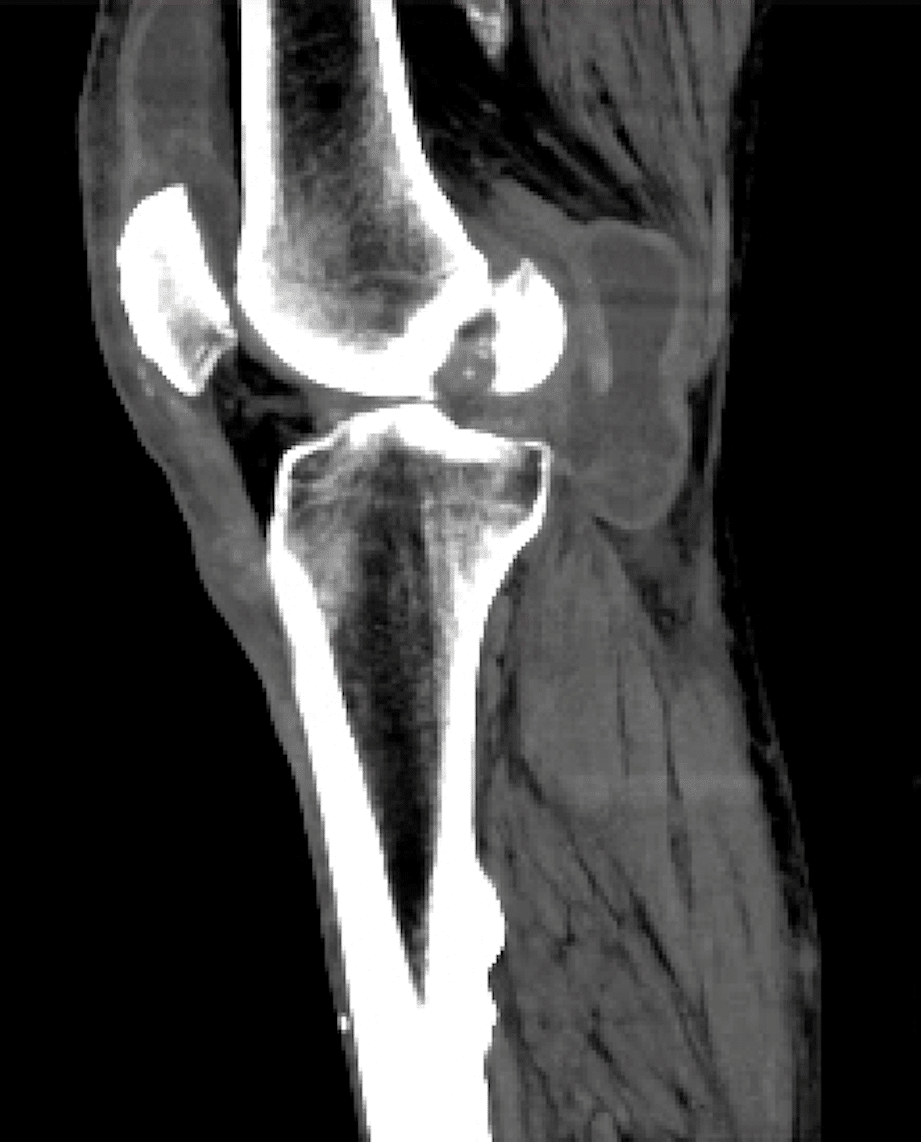

There are not many other reasons for such a fluid collection. But (ultrasound) reader beware! Masses behind the knee can look like cysts on ultrasound. A popliteal artery aneurysm can look like a small fluid collection as well. You have to make sure that there is no blood flow within the collection. Also, think about further imaging if anything does not fit a typical cyst. For instance, septations are allowed in a popliteal cyst. But if there are many septations or if the shape is unusual, it is best to obtain more imaging. For instance, with CT or (more commonly) MRI.